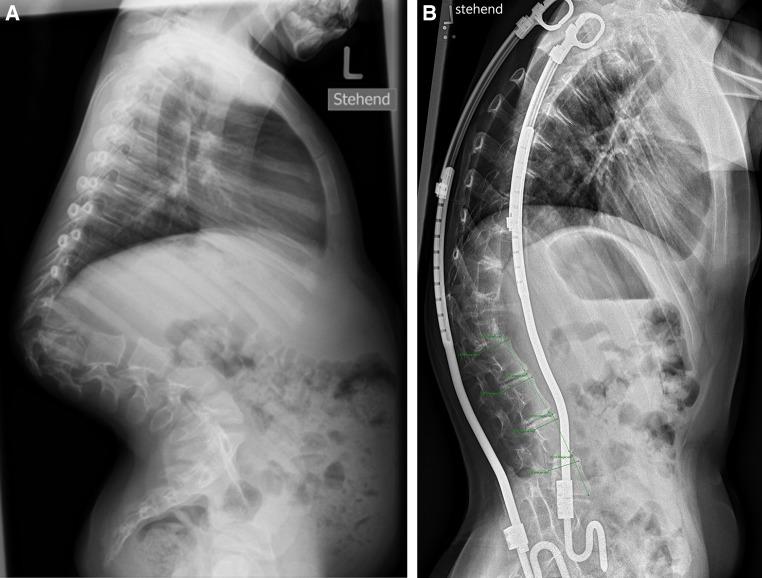

Metamorphosis of human lumbar vertebrae induced by VEPTR growth modulation and stress shielding.

METHODS

The goal of this retrospective radiographic study was to assess the growth modulating impact of year-long, distraction-based VEPTR treatment on the morphology of single vertebral bodies. We digitally measured lumbar vertebral body height (VBH) and upper endplate depth (VBD) at the time of the index procedure and at follow-up in nine patients with rib-to-ileum constructs (G1) spanning an anatomically normal lumbar spine. Nine patients with congenital thoracic scoliosis and VEPTR rib-to-rib constructs, but uninstrumented lumbar spines, served as controls (G2). All had undergone more than eight half-yearly VEPTR expansions. A Wilcoxon signed-rank test was used for statistical comparison of initial and follow-up VBH, VBD and height/depth (H/D) ratio (significance level 0.05).

RESULTS

The average age was 7.1 years (G1) and 5.2 year (G2, p > 0.05) at initial surgery; the average overall follow-up time was 5.5 years (p = 1). In both groups, VBH increased significantly without a significant intergroup difference. Group 1 did not show significant growth in depth, whereas VBD increased significantly in the control group. As a consequence, the H/D ratio increased significantly in group 1 whereas it remained unchanged in group 2. The growth rate for height in mm/year was 1.4 (group 1) and 1.1 (group 2, p = 0.45), and for depth, it was -0.3 and 1.1 (p < 0.05), respectively.

CONCLUSIONS

VEPTR growth modulating treatment alters the geometry of vertebral bodies by increasing the H/D ratio. We hypothesize that the implant-related deprivation from axial loads (stress-shielding) impairs anteroposterior growth. The biomechanical consequence of such slender vertebrae when exposed to unprotected loads in case of definitive VEPTR removal at the end of growth is uncertain.